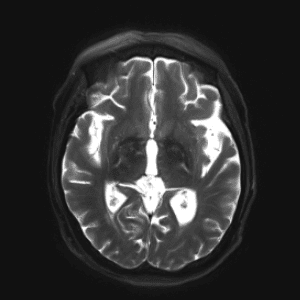

Neurodegenerative Diseases